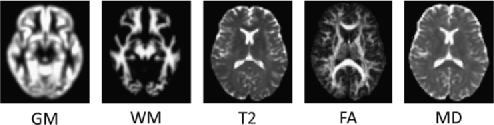

All images were screened by a trained radiologist and were examined for gross structural abnormalities, including white matter abnormalities. Diffusion tensor images were then preprocessed according to an in-house protocol and were summarized by measures of fractional anisotropy (FA) and mean diffusivity (MD) at every brain location [see Basser and Jones (2002)]. SPGR images were preprocessed using the DARTEL toolbox included in the SPM software package (www.fil.ion.ucl.ac.uk/spm), which involved nonlinear registration to a common reference space, segmentation into grey matter (GM), white matter (WM) and cerebrospinal fluid (CSF) in addition to smoothing with a 6mm isotropic Gaussian kernel.

For this analysis, whole-brain (unmodulated) GM and WM images derived from the SPGR scans, the T2 structural images plus the FA and MD images derived from the DTI sequence were used for classification, yielding a total of five distinct modalities for each subject. For illustrative purposes, an example of each type of image after preprocessing is provided in Figure 1.